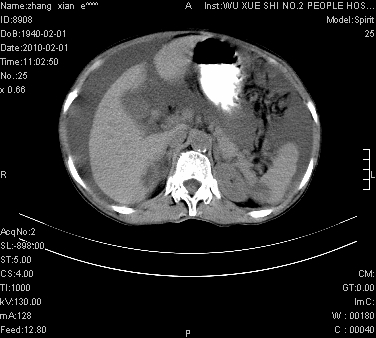

标题: CT24434:70岁 女 腹胀,腹水原因待查 [打印本页]

标题: CT24434:70岁 女 腹胀,腹水原因待查

大量腹水,脾脏囊性占位,子宫颈占位,右侧腹股沟淋巴结肿大,建议+c,先查妇科。

腹盆腔大量积液,子宫增大,子宫颈增大外形不规则,内见低密度影,膀胱后壁显示不清,右腹股沟肿大淋巴结,脾脏囊性占位,子宫颈占位,子宫颈癌?建议增强。

腹盆腔大量积液,子宫增大,子宫颈增大外形不规则,内见低密度影,膀胱后壁显示不清,右腹股沟肿大淋巴结,脾脏囊性占位,子宫颈占位,子宫颈癌?建议增强。支持!

大量腹水,右肾、脾囊肿可能性大          考虑左侧附件区占位,建议增强